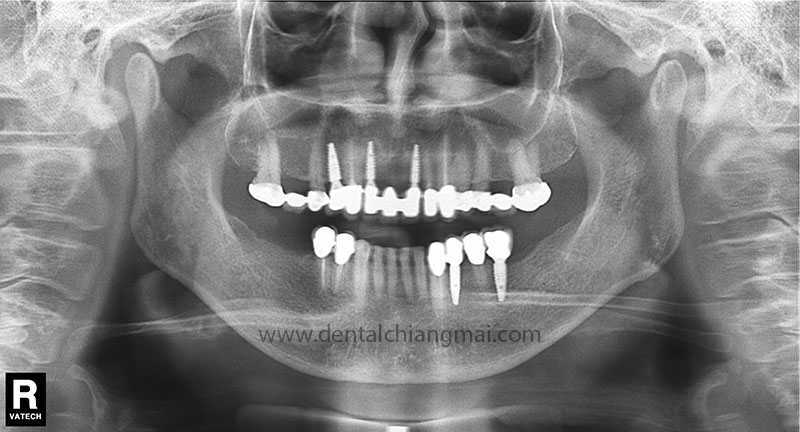

CASE 1 : 5 implants with 3 unit Bridges on upper front maxilla.

After: